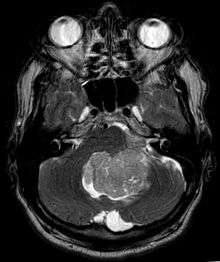

Ependymoma is a tumor that arises from the ependyma, a tissue of the central nervous system. Usually, in pediatric cases the location is intracranial, while in adults it is spinal. The common location of intracranial ependymoma is the fourth ventricle. Rarely, ependymoma can occur in the pelvic cavity.

Ependymomas are composed of cells with regular, round to oval nuclei. There is a variably dense fibrillary background. Tumor cells may form gland-like round or elongated structures that resemble the embryologic ependymal canal, with long, delicate processes extending into the lumen; more frequently present are perivascular pseudorosettes in which tumor cells are arranged around vessels with an intervening zone consisting of thin ependymal processes directed toward the wall of the vessel.[2]

Ependymoma tumors

Ependymomas make up about 5% of adult intracranial gliomas and up to 10% of childhood tumors of the central nervous system (CNS). Their occurrence seems to peak at age 5 years and then again at age 35. They develop from cells that line both the hollow cavities of the brain and the canal containing the spinal cord, but they usually arise from the floor of the fourth ventricle, situated in the lower back portion of the brain, where they may produce headache, nausea and vomiting by obstructing the flow of cerebrospinal fluid. This obstruction may also cause hydrocephalus. They may also arise in the spinal cord, conus medularis and supratentorial locations.[4] Other symptoms can include (but are not limited to): loss of appetite, difficulty sleeping, temporary inability to distinguish colors, uncontrollable twitching, seeing vertical or horizontal lines when in bright light, and temporary memory loss. It should be remembered that these symptoms also are prevalent in many other illnesses not associated with ependymoma.

About 10% of ependymomas are benign myxopapillary ependymoma (MPE). MPE is a localized and slowly growing, low-grade tumor. Although some ependymomas are of a more anaplastic and malignant type, most of them are not anaplastic. Well-differentiated ependymomas are usually treated with surgery. For other ependymomas, total surgical removal is the preferred treatment in addition to radiation therapy. The malignant (anaplastic) varieties of this tumor, malignant ependymoma and the ependymoblastoma, are treated similarly to medulloblastoma but the prognosis is much less favorable. Malignant ependymomas may be treated with a combination of radiation therapy and chemotherapy. Ependymoblastomas, which occur in infants and children younger than 5 years of age, may spread through the cerebrospinal fluid and usually require radiation therapy. The subependymoma, a variant of the ependymoma, is apt to arise in the fourth ventricle but may occur in the septum pellucidum and the cervical spinal cord. It usually affects people over 40 years of age and more often affects men than women.